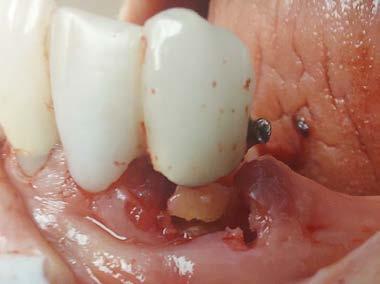

Cover: It’s a tricky situation. Patient with partial denture

Technique for extracting tooth or root tip from underneath fixed partial denture emphasizes use of magnification from dental loupes or dental surgical operating microscope for precision when performing technique-sensitive procedure. Case report.